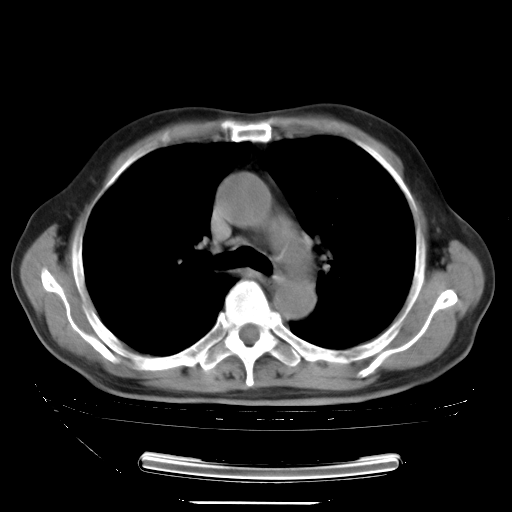

今天复查肺部CT,发现双肺广泛磨玻璃样改变。所以我把3月19日和5月9日相隔50天的肺部CT上传。请大家会诊。

2009年3月19日肺部CT片。

2009年3月19日肺部CT